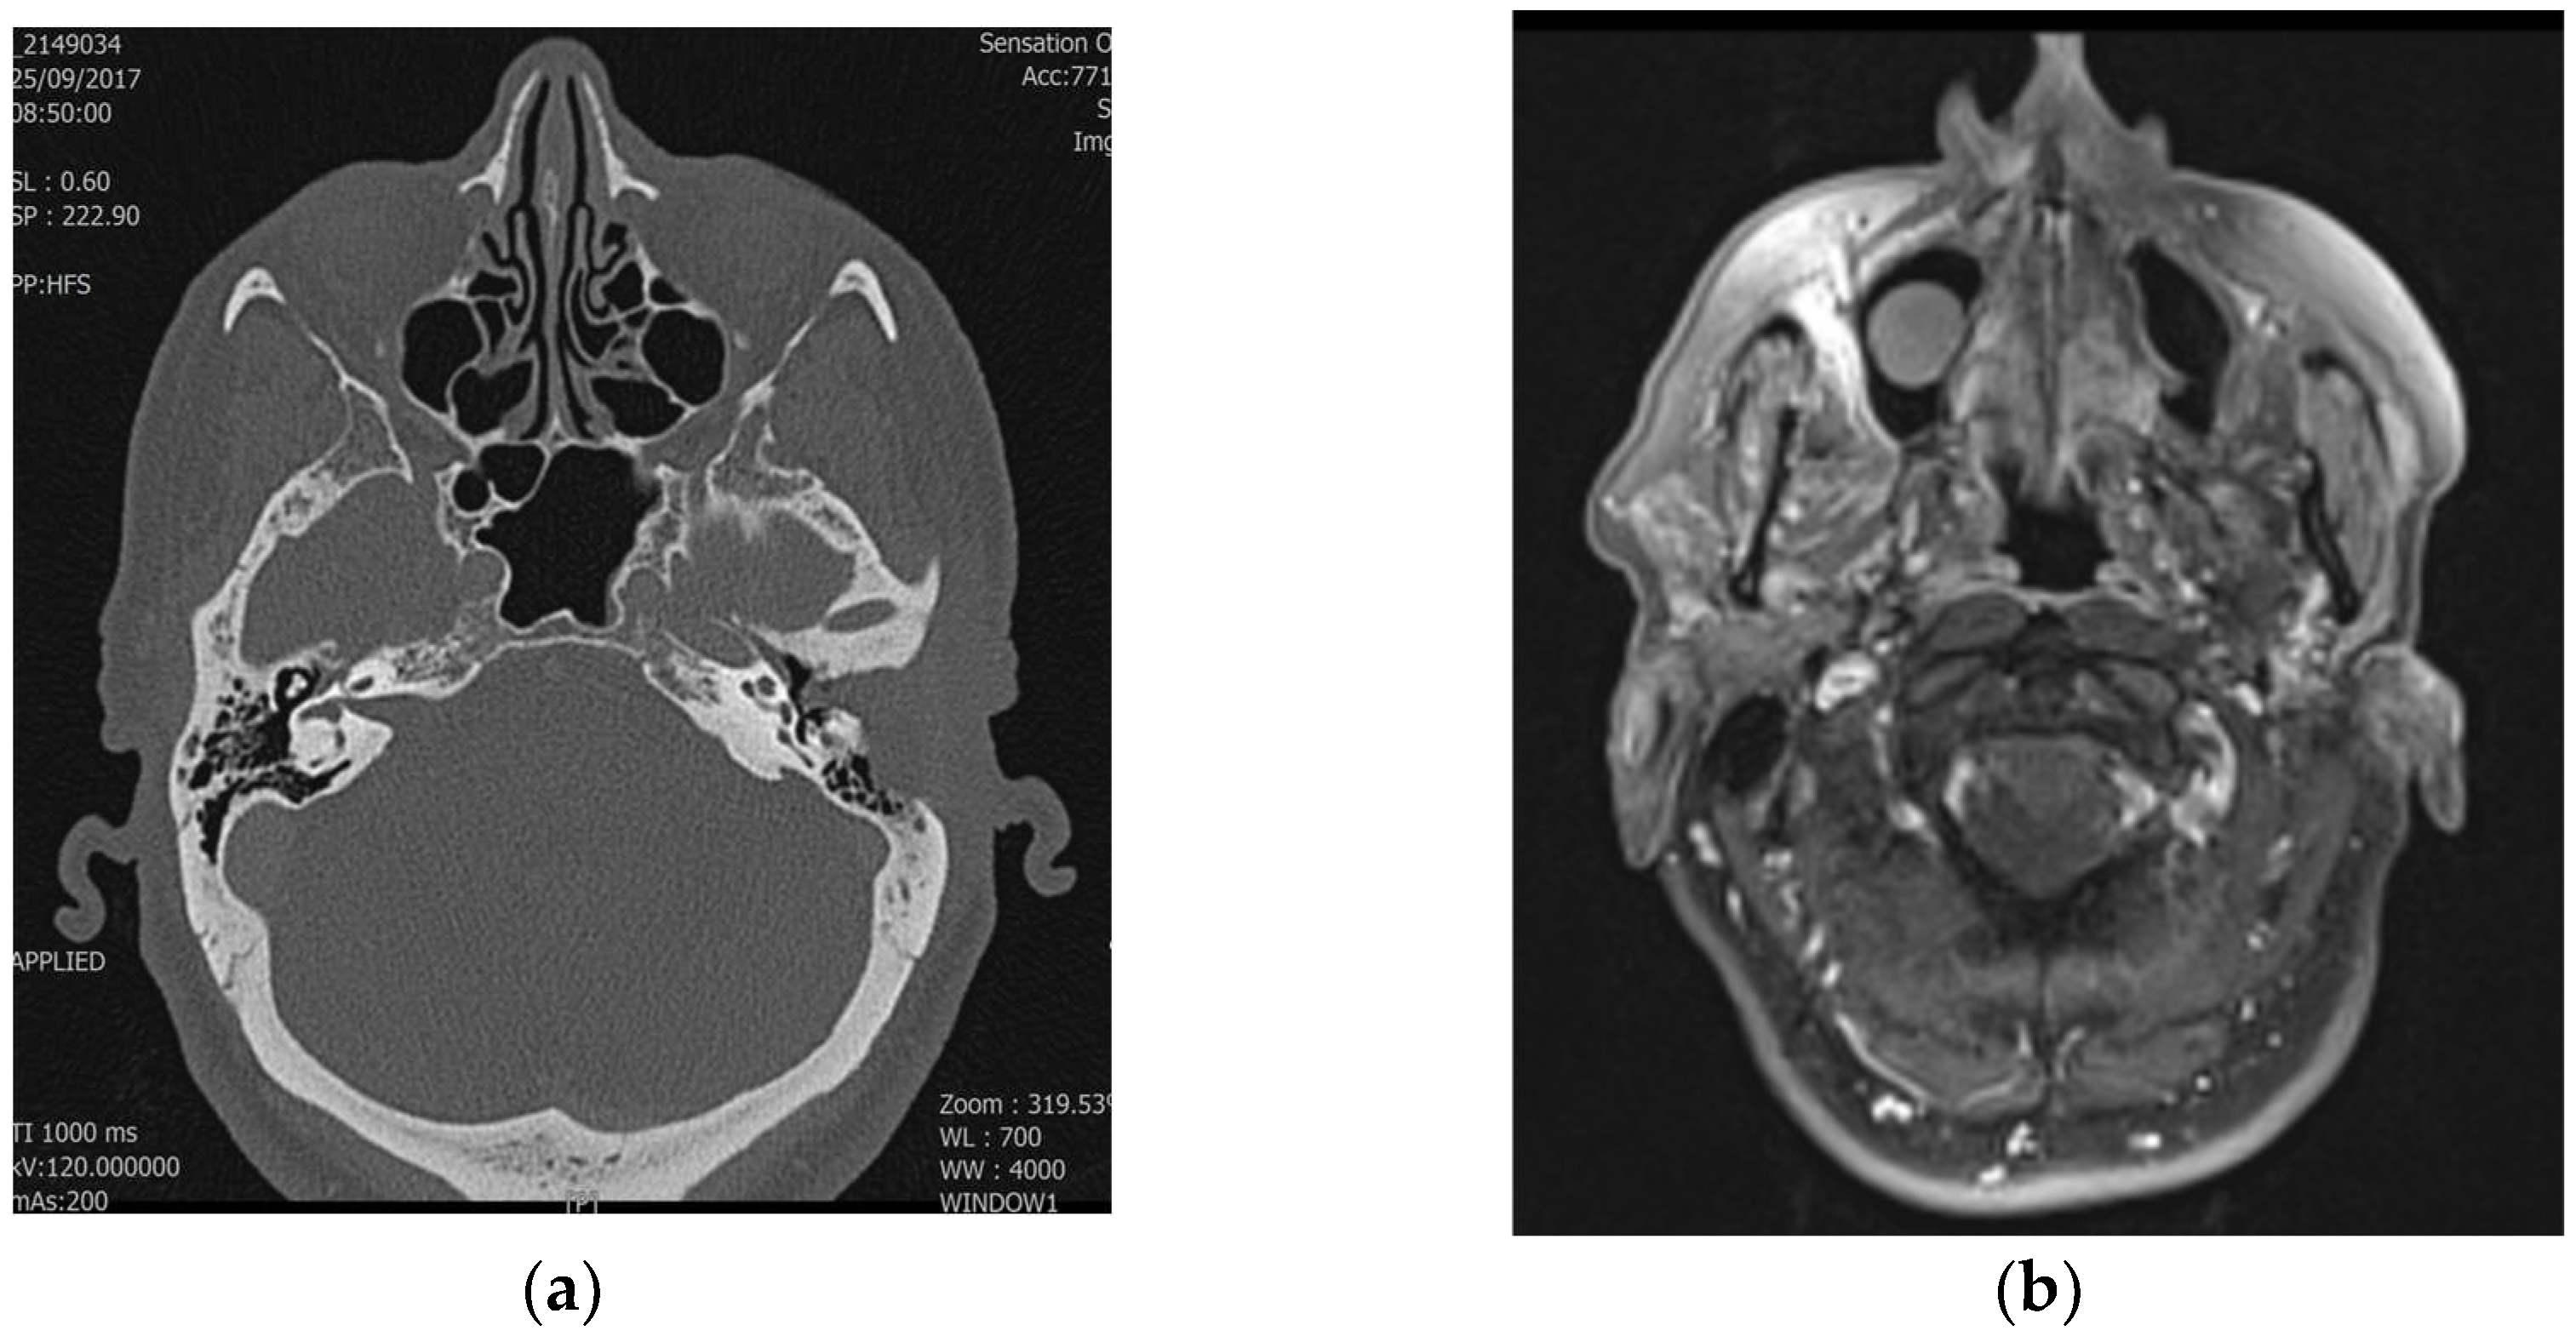

Figure 1. Axial MRI of the temporalis (a) in patients with SCC of the left EAC. The disease was classified as T1 by imaging, (b) but the final pathologic findings showed that it was T2 with bone erosion. The text continues here (Figure 2 and Table 2).

The preoperative radiological staging and the final pathological staging correlated in 11 (73%) of the 15 cases. The 73% correlation between radiologic and pathologic staging is remarkable and suggests a moderate level of reliability of the imaging modalities used. However, the discrepancies observed, particularly in cases where radiologic staging underestimated or overestimated pathologic findings, warrant further analysis. Factors such as the resolution limits of imaging techniques, variability in tumor presentation, radiologists’ experience, or ambiguous tumor features (e.g., small erosions or subtle soft tissue involvement) could contribute to these discrepancies. This finding could underscore the need for improving imaging protocols and staging accuracy with grids of observations. Radiological staging underestimated the stage in two cases and overestimated it in two others (Table 3). Table 3 highlights the discrepancies between radiological and pathological staging, illustrating cases where imaging underestimated or overestimated the tumor stage. These differences, seen in both T1–T2 and T3–T4 stages, emphasize the challenges in accurately determining tumor extent solely through imaging and underline the importance of multimodal evaluation to improve diagnostic precision (Figure 1 and Figure 2). Radiological staging correlated more frequently with pathological staging for T3 and T4 tumors compared to T1 and T2 tumors (86% vs. 63%). The Cohen’s Kappa value for evaluating the agreement between radiological and pathological staging was 0.66, indicating substantial agreement. This suggests a significant level of concordance between the two staging methods. Discrepancies may be attributed to the complexity of visualizing tumor extension through imaging or the possibility that some details were not easily identifiable with the imaging techniques. Therefore, a multimodal diagnosis, combining imaging and pathological evaluation, is emphasized to achieve accurate staging of temporal bone SCC.